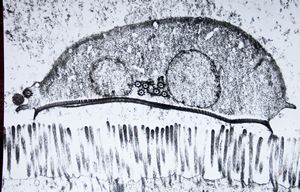

Giardia (lamblia) intestinalis